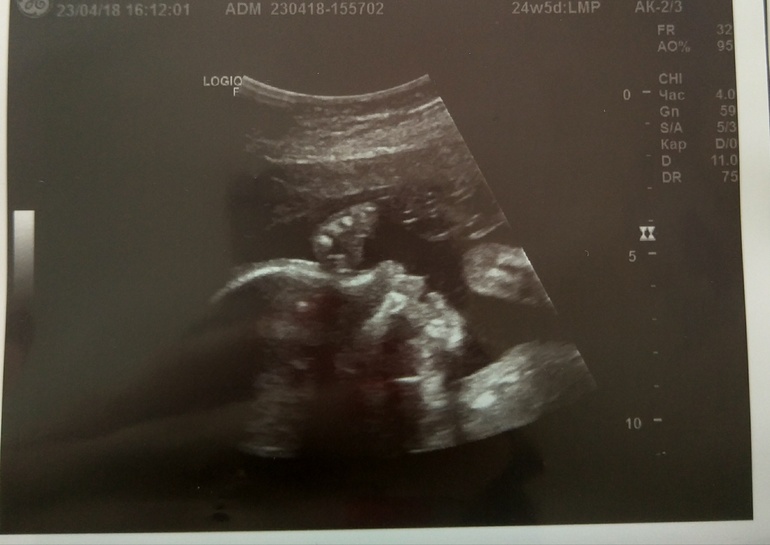

Рушана в Благополучная беременность 8 лет УЗИ УЗИ, КТГ, доплер 2 УЗИ пройдено...девчуля наша неугомонная.. всё УЗИ показывала кулачки.и перевернулась в головное.. Посмотрите еще 20 записей на эту тему Отменить Ответить Елена 14.05.2018 Ответить Рушана Спасибо !!! 15.05.2018 Ответить Dasa Ой, у меня тоже с ручкой :) Правда до сих пор сидит на попке!) 08.05.2018 Ответить Анна Ох, у меня до 30 недель туда сюда. То головой то попой вниз. Атас. 08.05.2018 Ответить Рушана Ну да..врач сказал ещё может 10 раз перевернуться ) 08.05.2018 Ответить AngelaMom какие они все таки разные даже на узи снимках))поздравляю с девочкой) 07.05.2018 Ответить Дарья Красотуля!)) 07.05.2018 Ответить Успокойте меня кто-то. ЧЛС почек плода Симфизит Чаты Беременных Выберите чат: Январята-2026 Февралята-2026 Мартята-2026 Апрелята-2026 Майчата-2026 Июнята-2026 Июлята-2026 Августята-2026